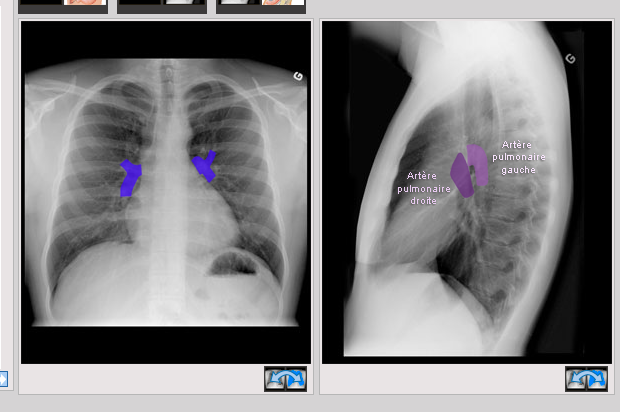

Où sont les hiles pulmonaires sur la radio?